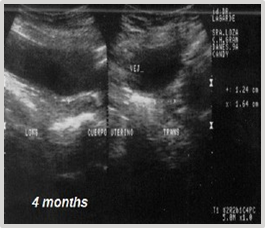

Evolution: The patient's progress occurs without significant clinical signs, except for mild hematuria. Symptomatic and ultrasonographic follow-up at 4, 6 months, and 1 year shows no recurrences (Figures 24) (Figure 25).

Figure 24 Ultrasonographic follow-up at 4 months post-cryosurgery.